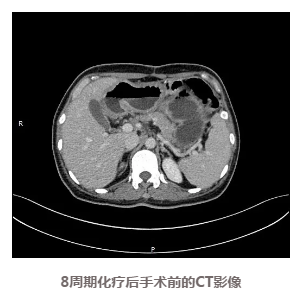

手术解决了梗阻问题,李女士的进食情况明显改善,逐步进流食、半流食、软食,直到可以少量多次进行基本正常饮食,体力状态和体重也逐渐恢复,根据方案进行了双药联合化疗,期间耐受性良好,复查CT显示肿瘤逐渐缩小。

患者的化疗取得了良好的治疗效果,通过检查评估肿瘤也已经明显缩小,此时到底是继续化疗还是选择手术治疗又成为了需要慎重选择的一个问题。为全面评估当前治疗效果,稳妥推进后续治疗,专家们再次为李女士进行了MDT(多学科会诊)

手术团队积极安排患者限期手术,先行腹腔镜探查发现,肿瘤与周围脏器无明显侵犯,可以手术切除,遂行开腹手术,最终成功进行了根治性切除。